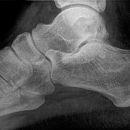

Calcaneus seitlich

Patient in Seitenlage, Fuß mit der Außenseite aufliegend, Ferse schwebt parallel zum Tisch.

Senkrecht auf Fersenbein bzw. 1-2 Querfinger unterhalb der Malleolen.

Qualitätskriterien

Seitliche Darstellung des Fersenbeins mit scharfen Knochenkonturen. Gut einsehbares unteres Sprunggelenk (Articulatio talocalcaneonaviculare) und einsehbares Gelenk zwischen Calcaneus und Os cuboideum.